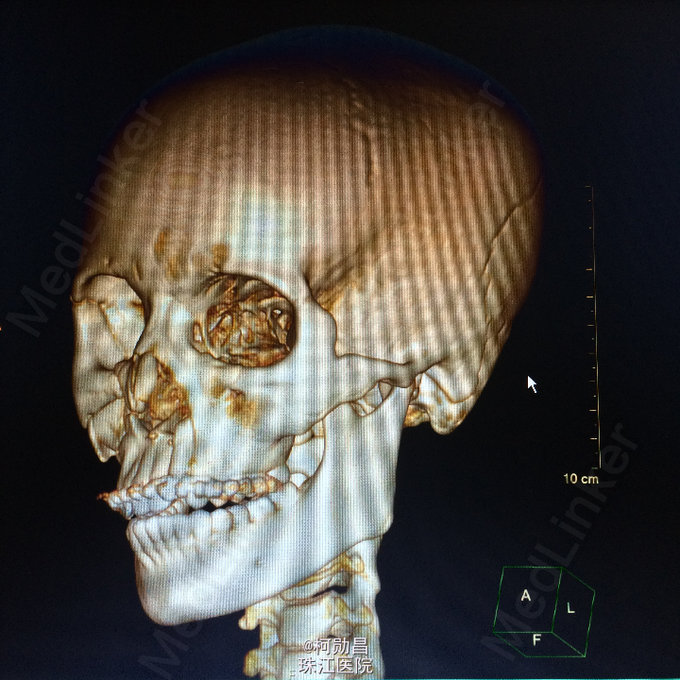

主诉:颅骨损伤后头痛、头晕2天 病史:患者于2天前骑摩托车时与机动车相撞,跌伤头部,至口角、眉弓处多处裂伤出血,左侧外耳道流血,当时患者无意识不清、肢体抽搐等。随即呼叫120送至医院。行头颅CT查示:左顶部硬膜下血肿,蛛网膜下腔出血,予相应治疗后病情稳定 。

查体:脑膜刺激征阳性 辅助检查:复查头颅CT及三维颅骨重建提示:血肿较前吸收,颅骨多发骨折,左额部较为明显

诊断:重型颅脑损伤,脑脊液耳漏、颅骨多发骨折